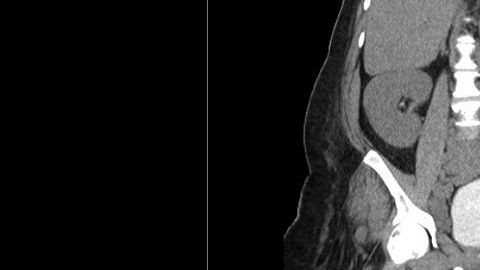

El hombre de 43 años acudió a los servicios de emergencia con fiebre alta, taquicardia y dos heridas abiertas en el escroto que goteaban pus. Los testículos se le hincharon progresivamente durante 30 años hasta llegar a pesar siete libras y medir alrededor de un pie, poco más que un balón de basquetbol. Debido al tamaño de sus genitales, el hombre sólo podía moverse con ayuda de una andadera y su madre le auxiliaba en las tareas cotidianas. Durante todo ese tiempo, no recibió ningún tipo de atención médica.

Además, de acuerdo con el Urology Case Reports que consignó el caso, el hombre sufría un linfedema (hinchazón) de grado cuatro y de tipo crónico en la ingle y la pierna derecha, condición que suelen sufrir las personas que padecen elefantiasis, un enorme absceso debajo de la piel que medía 12.8 centímetros y contenía gas, así como un riñón hinchado a causa de un reservorio de orina.